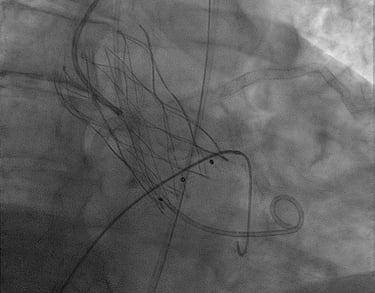

ANGIOPLASTICA

Angioplastica coronarica e lo stent

Si tratta del piu' comune trattamento attualmente utilizzato per curare l'aterosclerosi coronarica. E' una metodica che si avvale di molteplici strumenti appositamente ideati e realizzati e puo' essere effettuata subito dopo la coronarografia, utilizzando la stessa via di accesso arterioso. Solitamente, il paziente sottoposto ad angioplastica coronarica programmata puo' essere dimesso il giorno successivo alla procedura. Lo stent coronarico e' un dispositivo di grandezza millimetrica, in lega metallica biocompatibile (quindi senza fenomeni di rigetto), che viene utilizzato di solito dopo la dilatazione dell'arteria coronarica con il palloncino, per mantenere la pervietà della arteria.